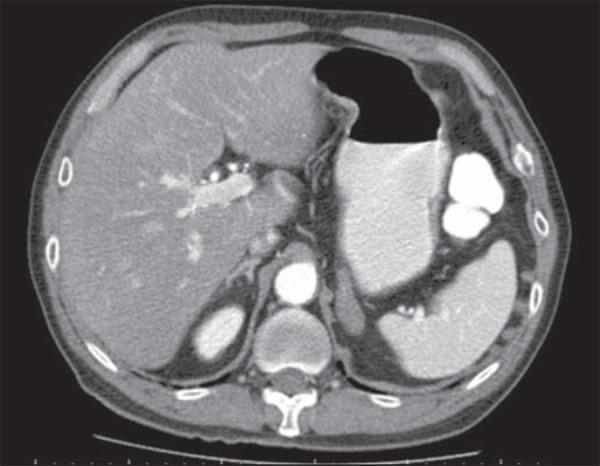

Abdominal alterations in disseminated paracoccidioidomycosis: computed tomography findings.

To evaluate the incidence and spectrum of abdominal computed tomography imaging findings in patients with paracoccidioidomycosis.

Retrospective analysis of abdominal computed tomography images of 26 patients with disseminated paracoccidioidomycosis.

Abnormal abdominal tomographic findings were observed in 18 patients (69.2%), while no significant finding was observed in the other 8 (30.8%) patients.

Computed tomography has demonstrated to play a relevant role in the screening and detection of abdominal abnormalities in patients with disseminated paracoccidioidomycosis.